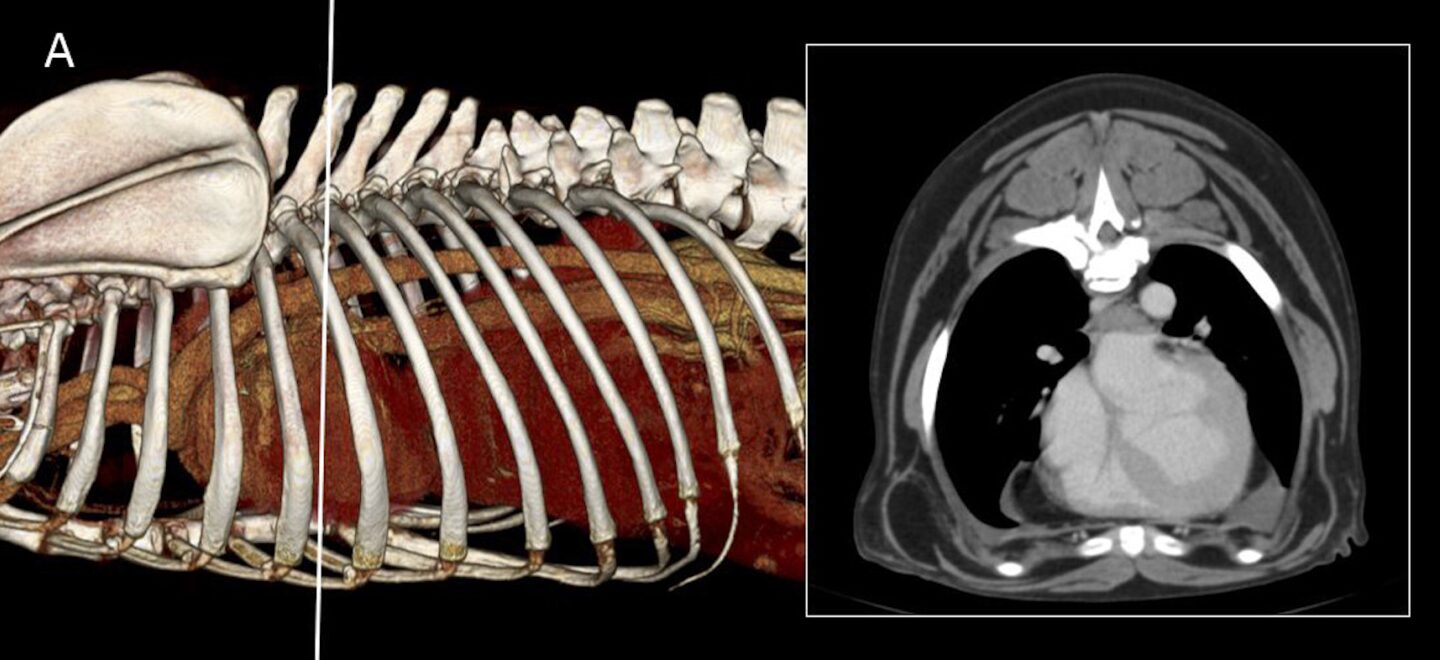

Soft and Heart Facts: Neue Aspekte der röntgenologischen Herzdiagnostik beim Hund

Ein Grundbilderpaar des Brustkorbs erlaubt in der Mehrheit der Fälle eine Herzerkrankung, welche mit einer Herzvergrößerung einhergeht, zu erfassen. Bis heute gibt es nur wenig medizinische Evidenz dafür, dass die Bestimmung der Herzgröße bezogen auf Wirbellängen im Vergleich zur subjektiveren Bildbeurteilung hilfreicher sind (1-3), Herzerkrankungen mit einer höheren Treffsicherheit zu erfassen. Messungen unt